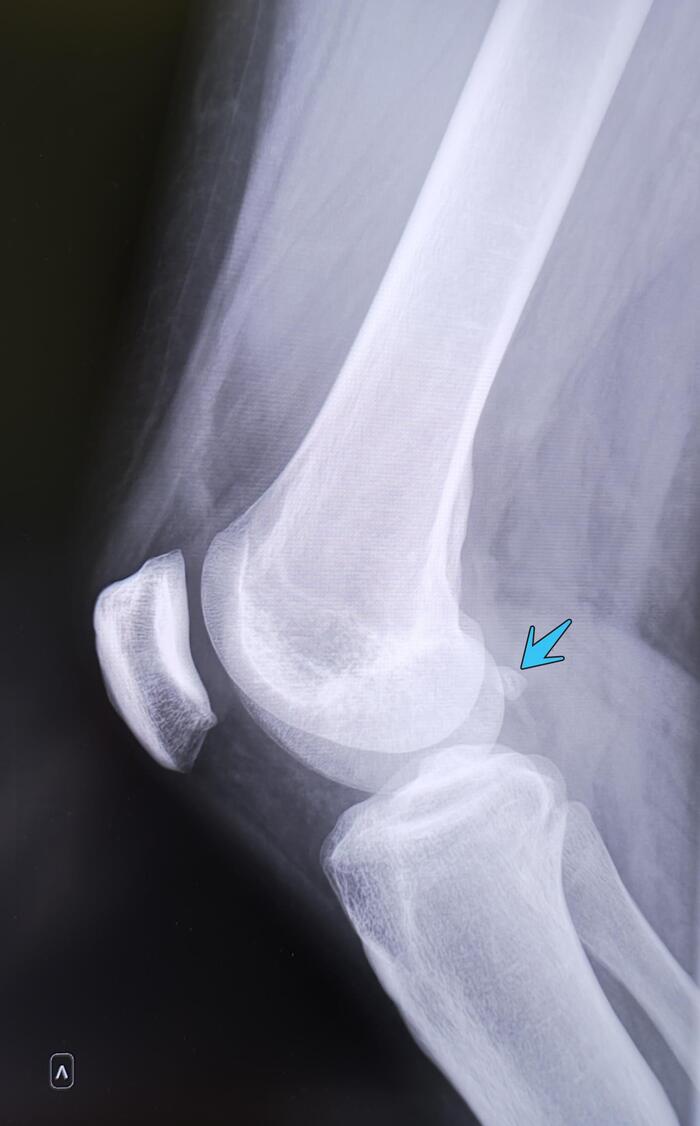

Из анамнеза-боли в левом голеностопном суставе при занятии спортом.

Описание: на Р-граммах левого гс/с в 2х проекциях суставная щель не сужена, субхондральный склероз, краевые остеофиты-не выявлены. По заднему контуру таранной кости определяется наличие дополнительной кости-os trigonum. Заключение:Os trigonum(аномалия развития левой стопы), наиболее вероятно вызывающая синдром компрессии таранной кости.

Категория годности с диагнозом Os trigonum(аномалия развития левой стопы), наиболее вероятно вызывающая синдром компрессии таранной кости-по статье 69г Б3-годен к военной службе с незначительными ограничениями.